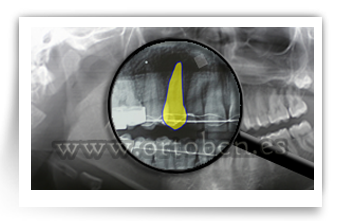

Ullal ectopic

Ectòpia